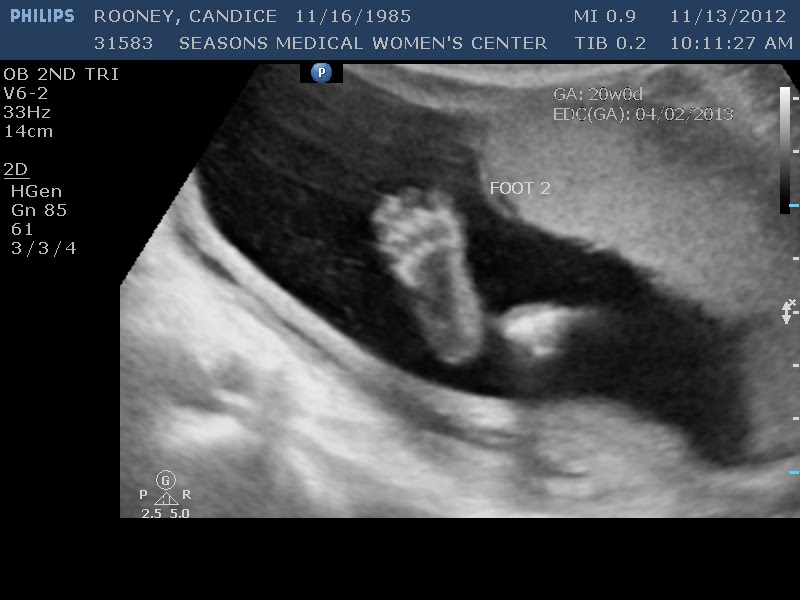

We actually got some cool pictures this time of her feet & hands & a amazing profile picture! I always cry seeing these pictures as they catch them. It really is amazing!